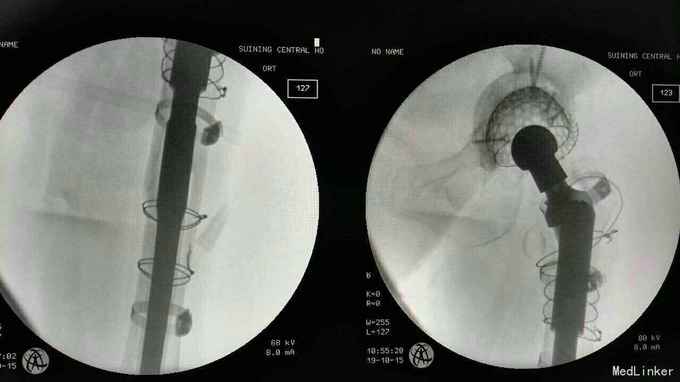

诊断:左髋关节置换术后假体松动; 右侧股骨头缺血坏死; 重度骨质疏松症 高血压病 压缩性骨折 治疗:左髋关节翻修术。(植骨、钛网骨水泥杯,骨水泥柄或翻修长柄MP(Link))

术中见骨质疏松明显,股骨劈裂,捆扎带固定。 术后股骨是否好愈合?